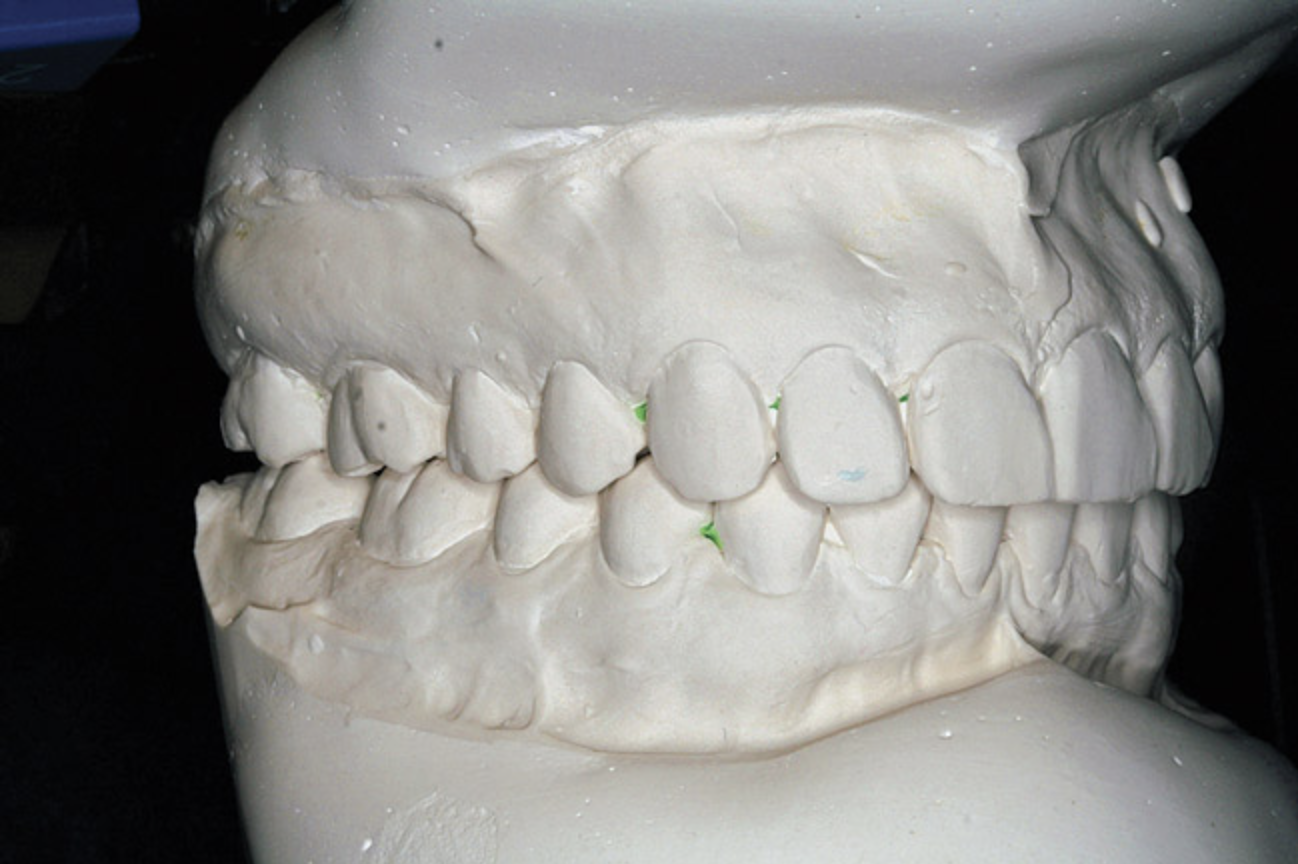

A stable TMJ is critical in establishing a normal functional occlusion. Unless the condyles are in a stable musculoskeletal position, there are always interferences to normal function and stress placed on the masticatory system.1-3,15 In orthodontics, the Angle classification of malocclusion using handheld models has been the standard to evaluate the fit of the teeth. However, it is not possible to truly identify the occlusion/malocclusion using handheld models. Before the occlusion can be evaluated, the clinician must ascertain the joint position and condition (Figure 7 and Figure 8).1,16

Figure 7A  This case is an example of the importance of evaluating the bite with the joints seated in a stable position. Orthodontic treatment was rendered to correct a

Figure 7A

Figure 7B  This case is an example of the importance of evaluating the bite with the joints seated in a stable position. Orthodontic treatment was rendered to correct a

Figure 7B

Figure 7C This case is an example of the importance of evaluating the bite with the joints seated in a stable position. Orthodontic treatment was rendered to correct a

Figure 7C

Figure 7D  This case is an example of the importance of evaluating the bite with the joints seated in a stable position. Orthodontic treatment was rendered to correct a

Figure 7D